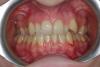

Layla Опубликовано 27 сентября, 2012 Поделиться Опубликовано 27 сентября, 2012 (изменено) Добрый день! Очень нужна консультация специалистов, т.к. я в полной растерянности. Так сложились обстоятельства, что процесс исправления прикуса я начала в другой стране и достаточно спонтанно.Мне 26, 5 лет. Была на консультации у 3 докторов, 2-ое из которых, не гляди на снимки с ходу сказали, что нужен аппарат RPE (в моем случае, как я поняла по фото, Хайрекс). 1 доктор советовал удалять. О хирургическом расширении никто из 3 не говорил.За 2 недели сделали аппарат и поставили почти 2 недели назад. Врач ничего толком не объяснила, ни планы лечения, ни возможные последствия, только сказала, что через пару дней я об аппарате забуду и что нужно раскручивать 3 раза в неделю.Я спросила, на сколько нужно расширить челюсть, она ответила -10 мм. Первые дни была сильная боль в области шестерок, на которых стоят кольца, жевать вообще не могла, да и до сих пор с трудом, челюсть не смыкается. Весь язык в ранах и не заживает , полоскания и сосательные таблетки от стоматита не помагают, слева верхние дуги врезаются в небо. результат -4 кг за неделю.Дикция ужасная, работа предполагает лекции на большие аудитории, не знаю , что делать. Пришлось самой начать изучать все в интернете.в итоге возникли вопросы по поводу адекватности лечения.Уважаемые специалисты, пожалуйста, посмотрите снимки , может вы сможете что-то порекомендовать.1. Нормально ли, что не попросили удалить 8-ки, хотя на нижней челюсти они в ужасном положении?2. Есть ли вероятность, что небный шов не разойдется и что делать в данном случае ? за почти 2 недели чувствую небольшое напряжение в переносице ( вроде как-то врач говорил, что искривлена) , щель между 1-ками не появляется.3. Какие могут быть негативные последствия расширения в моем возрасте?4. Можно ли в моем случае обойтись без удаления?5. Можно ли исправить прикус без хайрекса в моем случае или заменить его на что-то другое?6. Что делать с израненным языком, т.к. принимать пищу вообще не представляется возможным.7. И самое главное, как звучит мой диагноз?Родители просят название, а врач не сказала...Заранее огромное спасибо, очень жду ваших ответов и советов. Изменено 27 сентября, 2012 пользователем Layla Ссылка на комментарий

Force Опубликовано 30 сентября, 2012 Поделиться Опубликовано 30 сентября, 2012 34-36 - нормальное расстояние. В вашем случае экспансия может быть достигнута только с помощью брекет-системы. Расширение хайрексом чревато последствиями, три-четыре оборота назад обвчно делают. Рекомендую обсудить с вашим лечащим доктором. Диагноз ваш - бимаксилярная ретрузия, сужение зубоальвеолярных дуг, тесное положение зубов верхней и нижней челюстнй.Удаление восьмерок внизу критично. Ссылка на комментарий